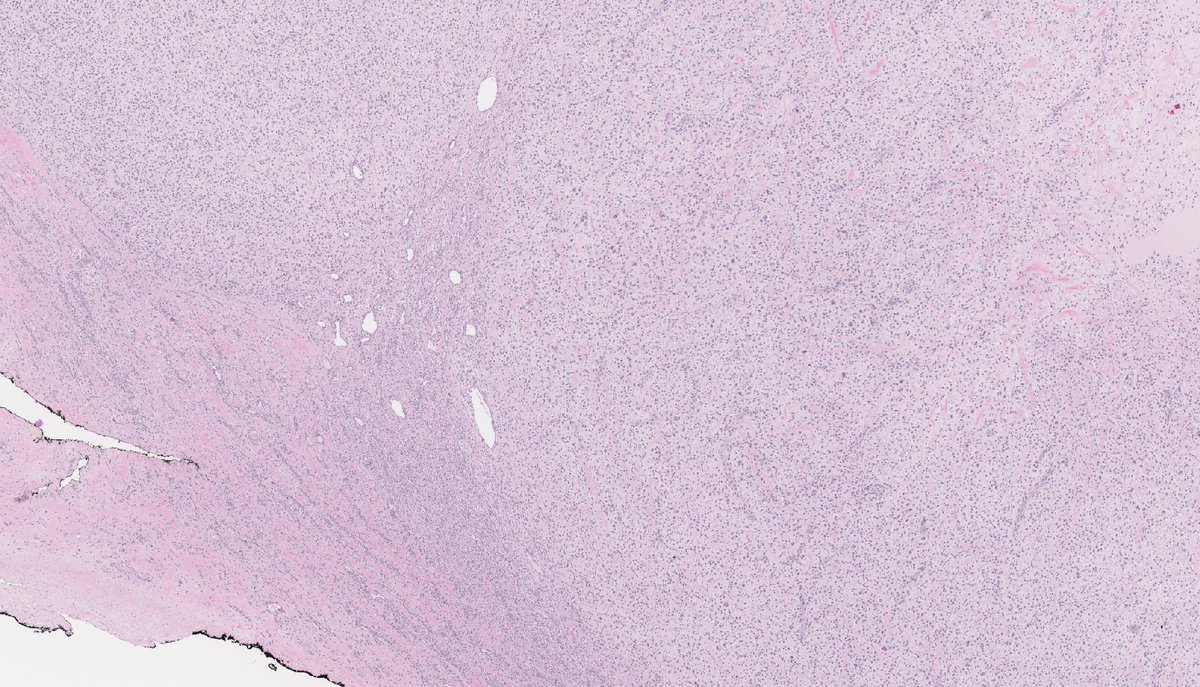

Anatomical Pathologist - UBC #BSTpath #GYNpath